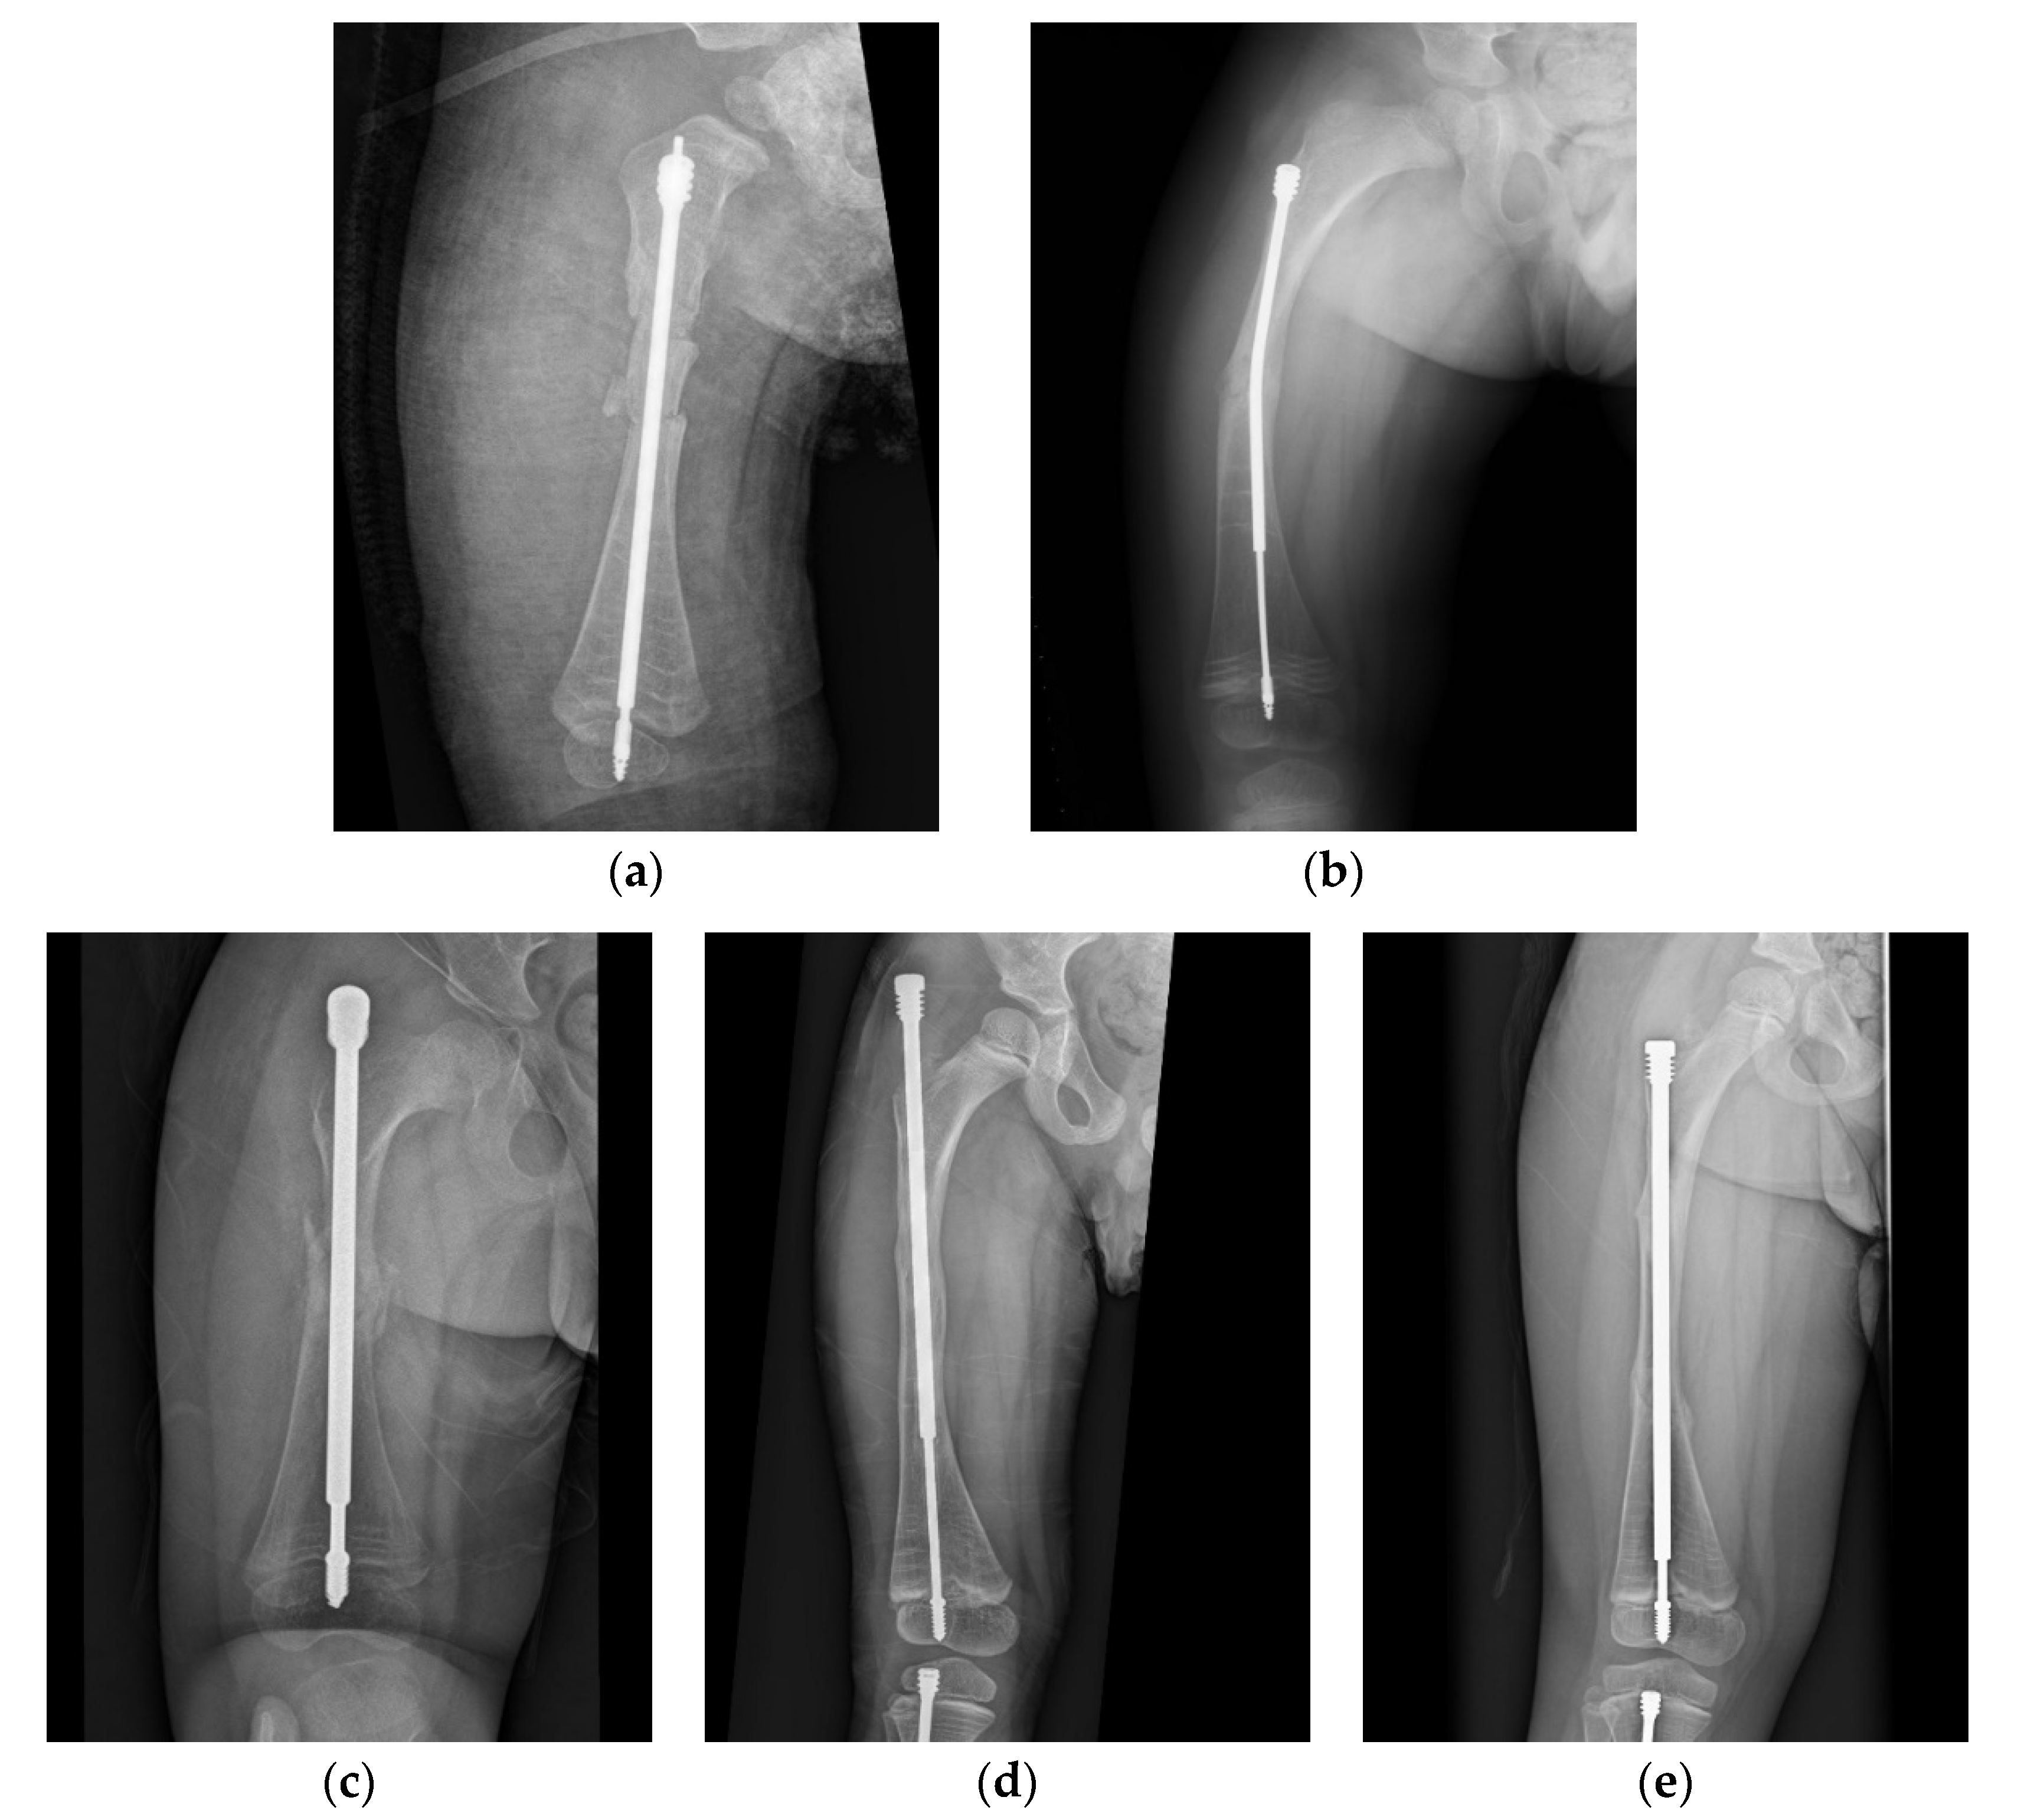

Another of our cases involved a boy who received double osteotomies and fixation with an FD nail in his right femur at the age of 1.5 years (Figure 3). The proximal osteotomy segment was too small to align and the greater trochanter had not ossified, so it was difficult to find the most suitable entry point under the c-arm (Figure 3a). During follow-up, we found that the female thread had become much more distal and anterior (Figure 3b). In the following revision, due to concerns over damaging the apophysis of the femur and iatrogenic greater trochanter epiphysiodesis, with resulting sequela of valgus deformity, insufficient depth of the female component may have occurred, resulting in its proximal protrusion (Figure 3c,d). The importance of the entry point and adequate purchase of the proximal femur cannot be over-emphasized (Figure 3e).

Figure 3. Anteroposterior (AP) view radiograph of the femur of a 1.5-year-old male post FD nail implantation. (a) The boy received double osteotomies and fixation with an FD nail in the right femur. The proximal fragment was extremely small and difficult to control, and the greater trochanter had not yet been ossified, so it was a huge challenge to find the most suitable entry point under the c-arm. We can see the entry point was anterior to the true position of the greater trochanter. (b) During regular follow-up, we found that the female thread had become much more distal and anterior with nail bending. (c) In the revision surgery, due to concerns over damaging the apophysis of the femur in order to avoid physis fusion and valgus deformity, we may have used insufficient depth of the female component. (d) During regular follow-up, we found proximal protrusion of the female component. (e) Good position and adequate purchase of the FD nail post revision surgery.